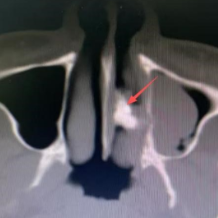

接诊的杨中纯副主任医师为李可进行鼻内镜检查时发现,其左侧鼻腔底部有一处呈粉色肉芽状的隆起,肉芽底部质地偏硬,呈现出沙砾样变化,表面并不光滑。与此同时,医生还检查了李可的口腔,奇怪的是,他口腔内牙齿完好,且并无严重的鼻部外伤史。这个“硬家伙”究竟是什么呢?为进一步揭开谜团,医生为李可进行了鼻腔CT检查。结果令人大吃一惊,这个困扰他多年的“鼻内硬物”——竟是一颗鼻腔异位牙!

箭头所指的就是鼻腔异位牙